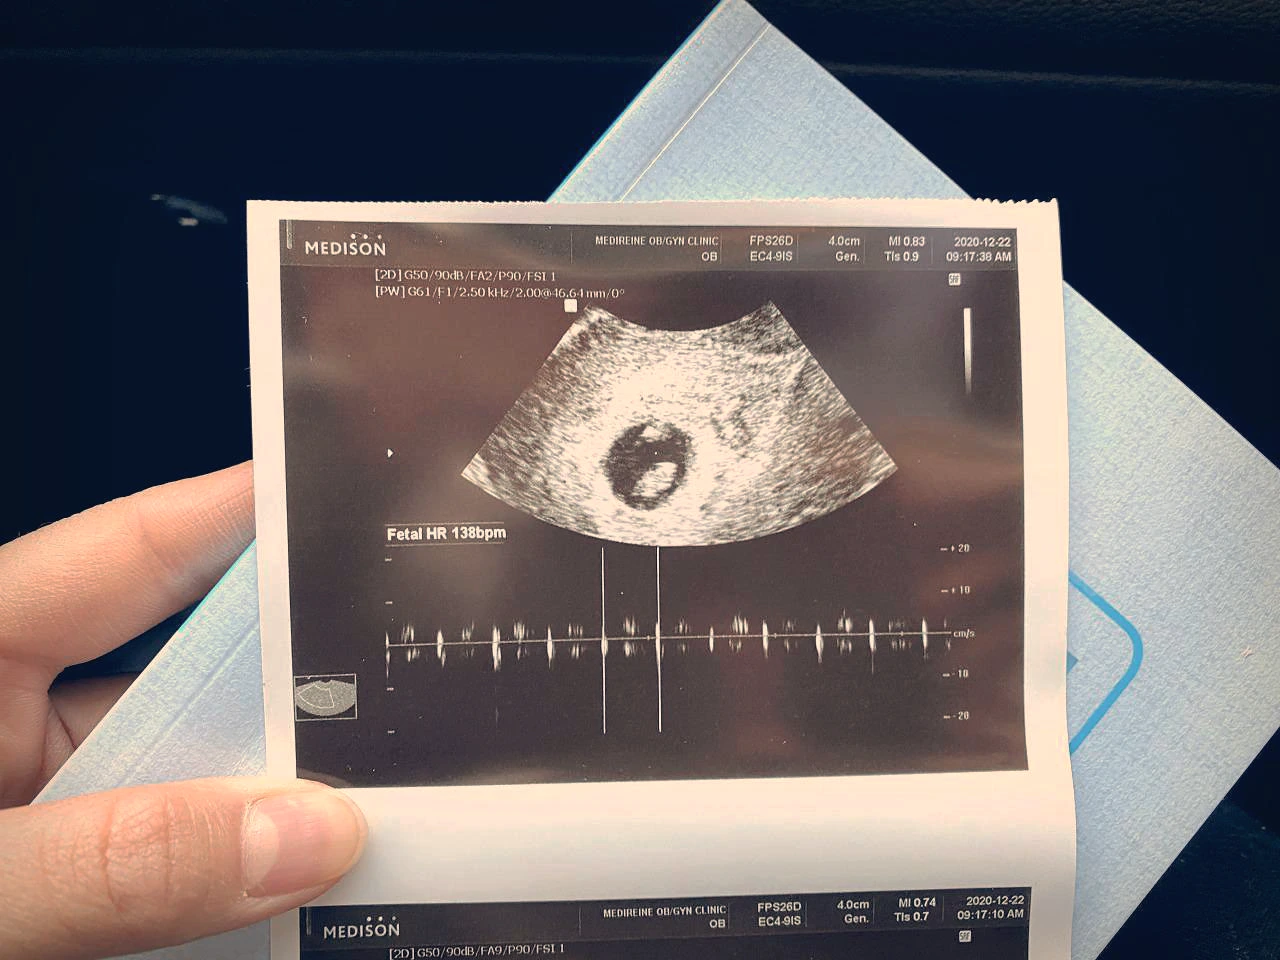

아이를 낳고 오랜만에 컴퓨터 앞에 앉았다. 34년의 인생에서 '엄마'라는 역할 하나가 더 해졌을 뿐인데 이 두 글자가 주는 무게가 꽤 무겁고 단단해서 그동안 내가 해오던 모든 것들에 잠시 일시정지 버튼을 누르지 않고서는 정신을 차릴 수 없었다. 8월 11일에 세상에 나오기로 했던 2.4킬로의 아기는 태명처럼 8월 첫째 날 샛별이 뜨는 시간을 앞두고 태어났다. 출산의 고통은 지금까지 으레 들어왔던 (혹은 상상해왔던) 고통과 차원이 다른 무엇이어서 나는 꽤 오랜만에 '포기'라는 단어를 떠올렸다. (그간 내가 도전한 것이 없다는 의미이기도 했다.) 자정을 넘기자 진통은 점차 그 주기가 짧아지고 있었고 고통이 밀려올 때마다 아기 심박수가 떨어지고 있었다. 이대로라면 실컷 진통으로 고생을 하고 결국 제왕절개를 하는 결론을 마주해야 했기에 나는 젖 먹던 힘을 다해 아기를 밀어냈다. 그렇게 3시간의 사투 끝에 샛별이는 세상 밖으로 나왔다. 초산의 평균 시간이 11시간 정도임을 생각하면 비교적 빨리 아이를 낳은 셈이었다.